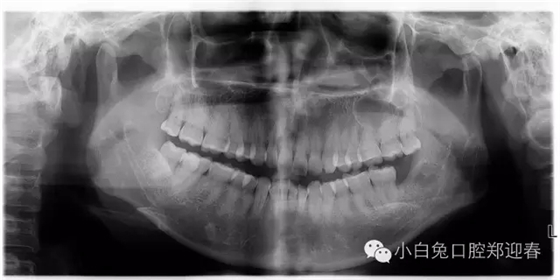

術(shù)后的全景片

一例智齒斷根進行二次拔除的感悟